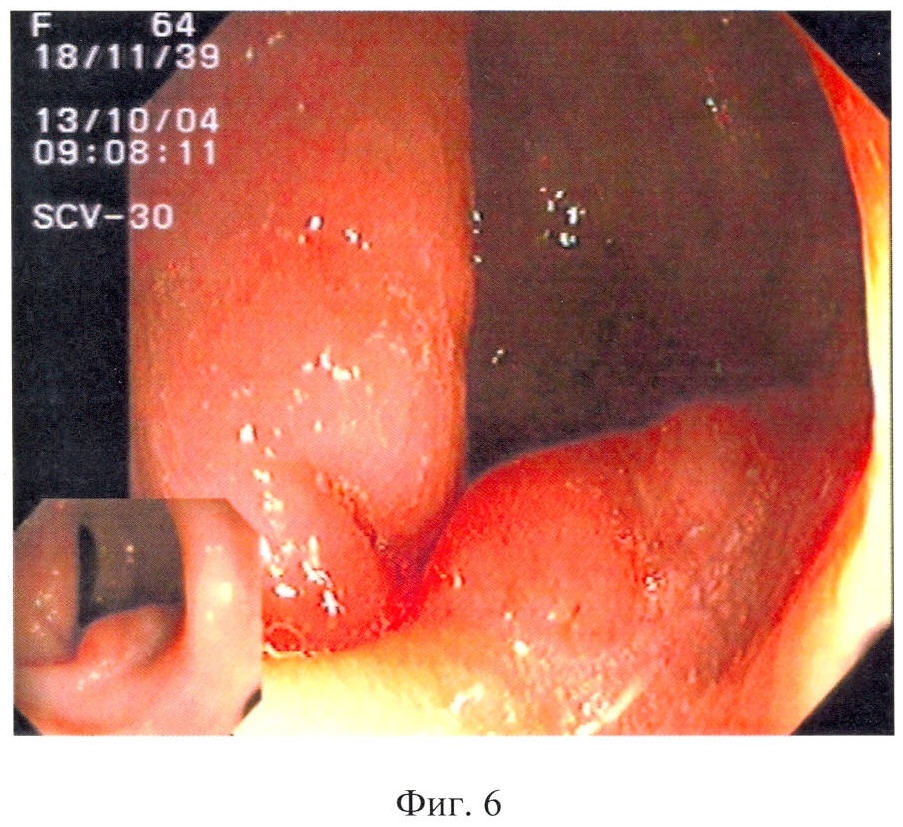

Способ поясняется следующими чертежами, где на фиг.1 показан полип области печеночного изгиба, суммарный балльный критерий более 179: а – при максимальном приближении дистальной головки и линзы колоноскопа, б – после биопсии; на фиг.2 – полип сигмовидной кишки, суммарный балльный критерий до 178 баллов (клинический пример 1); на фиг.3 – полип сигмовидной кишки, суммарный балльный критерий более 179 баллов, на фиг.4 – гистологический срез полипа сигмовидной кишки, окраска гематоксилин-эозином (клинический пример 2); на фиг.5 – полип сигмовидной кишки, суммарный балльный критерий до 178 баллов, на фиг.6 – полип сигмовидной кишки через 10 месяцев после первого обследования, суммарный балльный критерий более 179 баллов (клинический пример 3), а также табл.1, где перечислены эндоскопические признаки, их градации и числовые значения, используемые для вычисления суммарного балльного критерия, и табл.2, где показана морфологическая характеристика полипа и лечебная тактика в зависимости от суммарного балльного критерия исследования.

В нижней трети сигмовидной кишки расположен полушаровидный полип до 0,2 см в диаметре, розовый, гладкий, не реагирует на инструментальную пальпацию (фиг.2).

По выявленным признакам вычислен суммарный балльный критерий:

Критерий = группа по размеру + эндоскопический тип + цвет + форма + поверхность + ранимость = 21+44+17+12+12+7=113 баллов.

В соответствии с предложенным авторами критерием было дано заключение о наличии доброкачественного морфологического строения полипа. Взята биопсия. При гистологическом исследовании – гиперпластический полип.